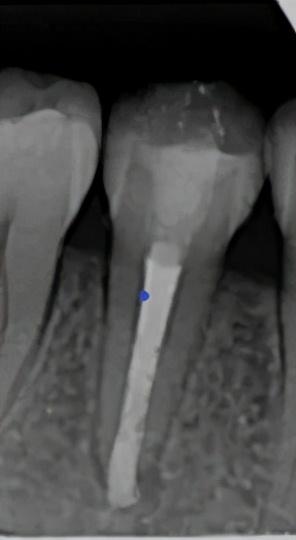

2 热牙胶充填

半年复查根尖片

半年后根尖片复查,根尖暗影明显缩小,几乎快要痊愈了,要挺住啊!继续期待一年的复查效果。